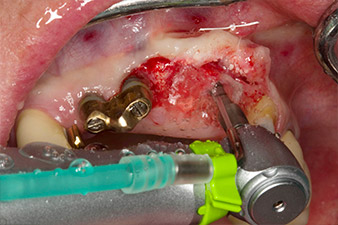

Enroscado mecánico del implante con el contra-ángulo WS-75 L

Imagen 4: Enroscado mecánico del implante con el contra-ángulo WS-75 L con una transmisión de 20:1 (programa P5).